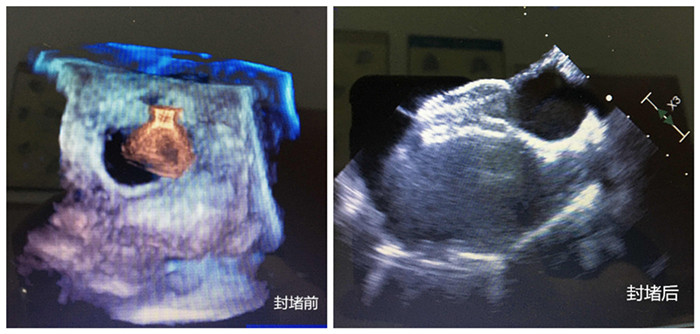

無影燈下,主刀醫(yī)生周珉在小強(qiáng)的右腋下切了一個(gè)長度為4cm左右的切口,隨后,在經(jīng)食管探頭的引導(dǎo)下,封堵器順利通過心臟缺損部位,完成釋放和固定,牢牢地堵住缺口,“心臟正常的血液循環(huán)途徑恢復(fù)!”僅30分鐘,小強(qiáng)的心臟修補(bǔ)成功。

封堵前、封堵后兩張圖

守在手術(shù)室外的家人表示難以置信。三天后,小強(qiáng)便順利出院。